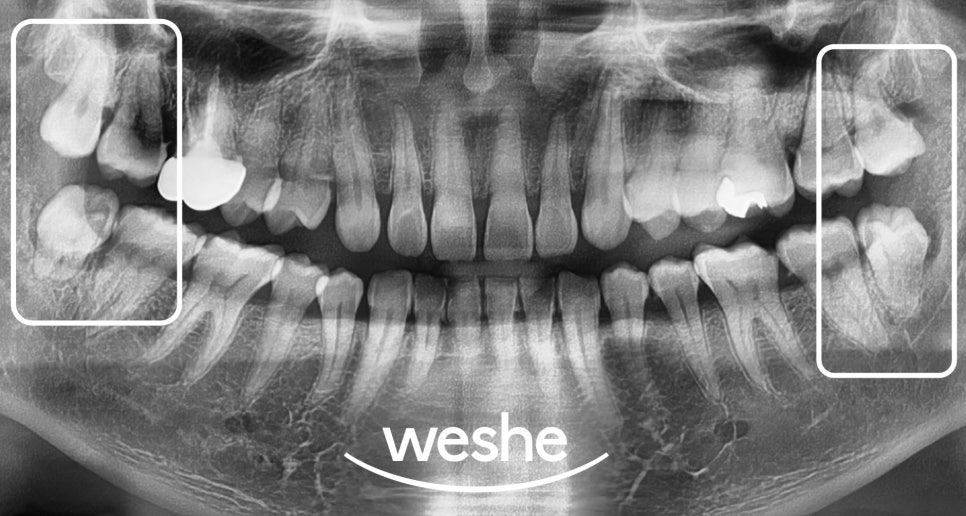

엑스레이 검사를 통해서는

사랑니 주변 염증 상태와

매복 정도를 정확히 파악할 수 있습니다.

네 개의 사랑니(18, 28, 38, 48)에서

관리가 되지 않아 주위 치석과 염증, 충치가

진행되어 발치가 필요하다 판단됩니다.